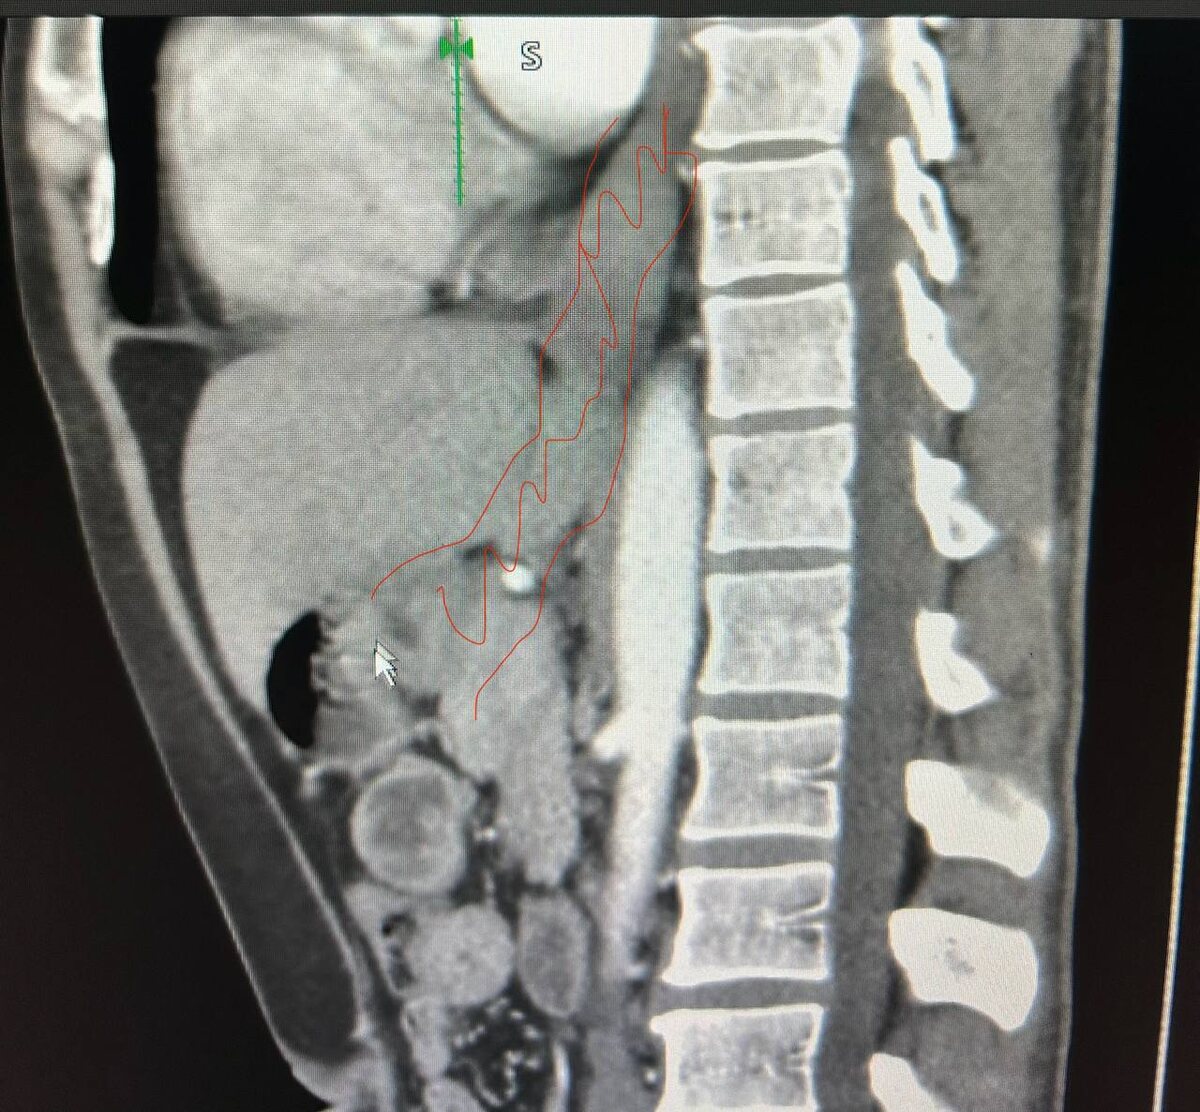

На этой неделе у нас была действительно непростая операция. Молодой пациент (40 лет) столкнулся с агрессивной опухолью, которая распространилась сразу на пищевод и желудок. В такой ситуации стандартные методы лечения были невозможны, и нам пришлось принять радикальное решение.

• Мы удалили практически весь желудок и значительную часть пищевода.

• Чтобы пациент мог полноценно питаться, мы использовали толстокишечный трансплантат, который заменил удаленные органы.

Как это работает? Уже на вторые сутки после операции пациент выпил контрастное вещество, и рентгенография показала, что:

• Оно сначала проходит по пищеводу.

• Затем попадает в трансплантат из толстой кишки.

• Далее – в оставшуюся часть желудка.

• И, наконец, в тонкую кишку.

🔍 В посте прикрепляем рентген-снимок и схему операции для наглядности.